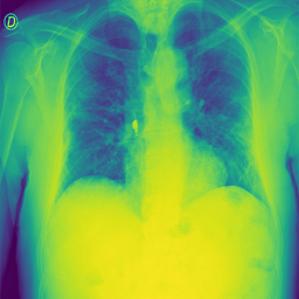

These steps collectively enhance the critical features of the CXR images, aiding in more accurate analysis. Figure2 shows the comparison between CXR images before and after preprocessing highlighting the enhanced clarity and feature extraction achieved through the applied filters.

Figure 2: Comparison of CXR Images Before and After Preprocessing